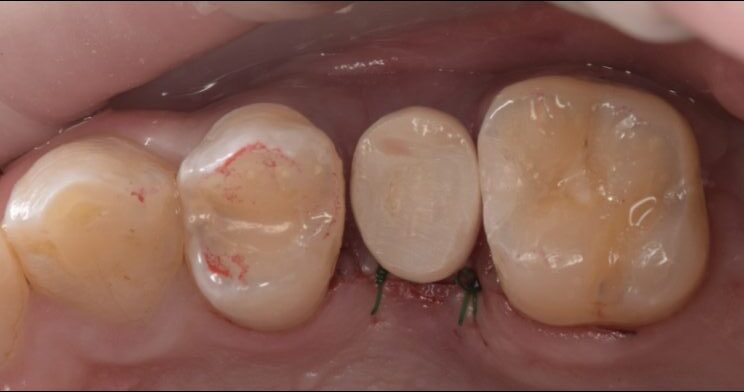

インプラント埋入後は、なるべく仮歯をSETしQOLを下げないようにしております。

オペから8週後に印象を行います。

上部構造物(セラミック)をSETします。